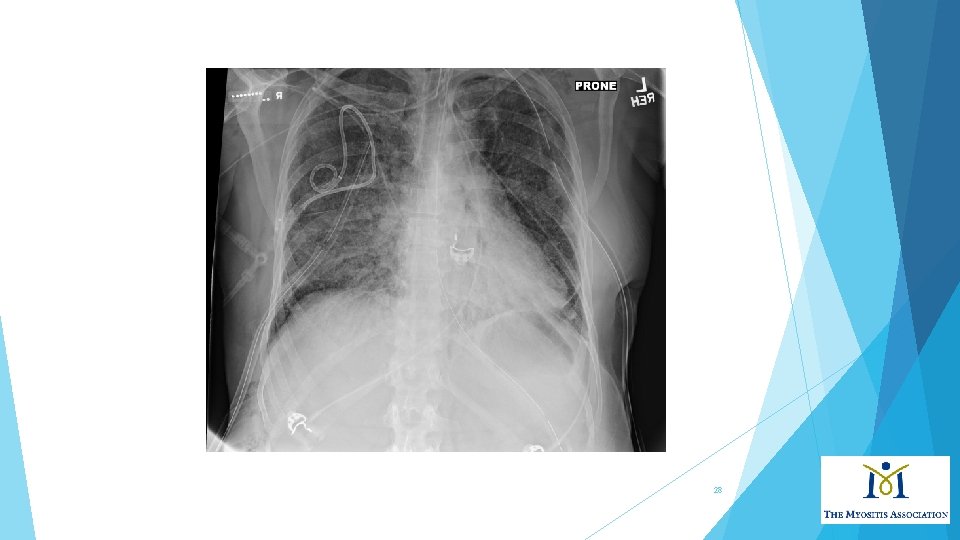

How are different people affected? Patient 3. 57 yo white woman presented to clinic with rashes over face, chest, hands inflammatory arthritis involving small joints of hands and dyspnea Skin biopsy revealed “vacuolar interface dermatitis” Chest x-ray showed bi-basilar infiltrates Within 2 weeks of presentation, admitted to ICU with acute respiratory failure Intubated, started on treatment for myositis and lung disease, and after 2 weeks hospitalization, died 27

28

Dermatomyositis and pulmonary manifestations • At least 30% myositis patients have interstitial lung disease (ILD) This may manifest as fatigue and dry cough, shortness of breath that gets worse with minimal activity Patients also may have respiratory muscle weakness Anti-Jo-1 antibody found in 50 -75% myositis pts with ILD • Strong association of ILD with all anti-synthetase antibodies in myositis. No correlation between extent and severity of muscle or skin disease and development of ILD. Secondary pulmonary hypertension can occur due to chronic pulmonary vasoconstriction from hypoxemia. 29

Dermatomyositis and pulmonary manifestations Onset of ILD variable: most of the time occurs at the same time of myositis diagnosis. Course ranges from acute and fulminant ILD, chronic progressive, or asymptomatic (subclinical). Pulmonary function testing reveals restrictive physiology (i. e. FVC ≤ 80%). ILD subtype classified as non-specific interstitial pneumonia (NSIP)—most common, cryptogenic organizing pneumonia (COP), and usual interstitial pneumonia (UIP). Chest imaging shows basilar abnormalities: reticular and ground-glass opacities with loss of lung volume, traction bronchiectasis ILD leads to poor functional status in 30% of patients. 30